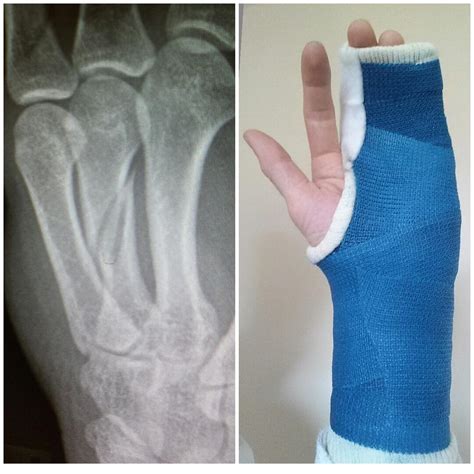

Broken Hand Cast

When a physician places a broken hand cast, they are essentially creating a rigid shell that prevents movement in the affected area. By restricting the joints around the fracture, the cast ensures that the bones are not disturbed during the critical stages of ossification. Most casts are made from either plaster or fiberglass, both of which serve the same goal: structural support.

• Fiberglass casts: These are lightweight, breathable, and come in various colors. They are durable and set quickly.

• Plaster casts: These are heavier and take longer to dry but are often preferred for initial swelling, as they can be molded more precisely to the patient's anatomy.